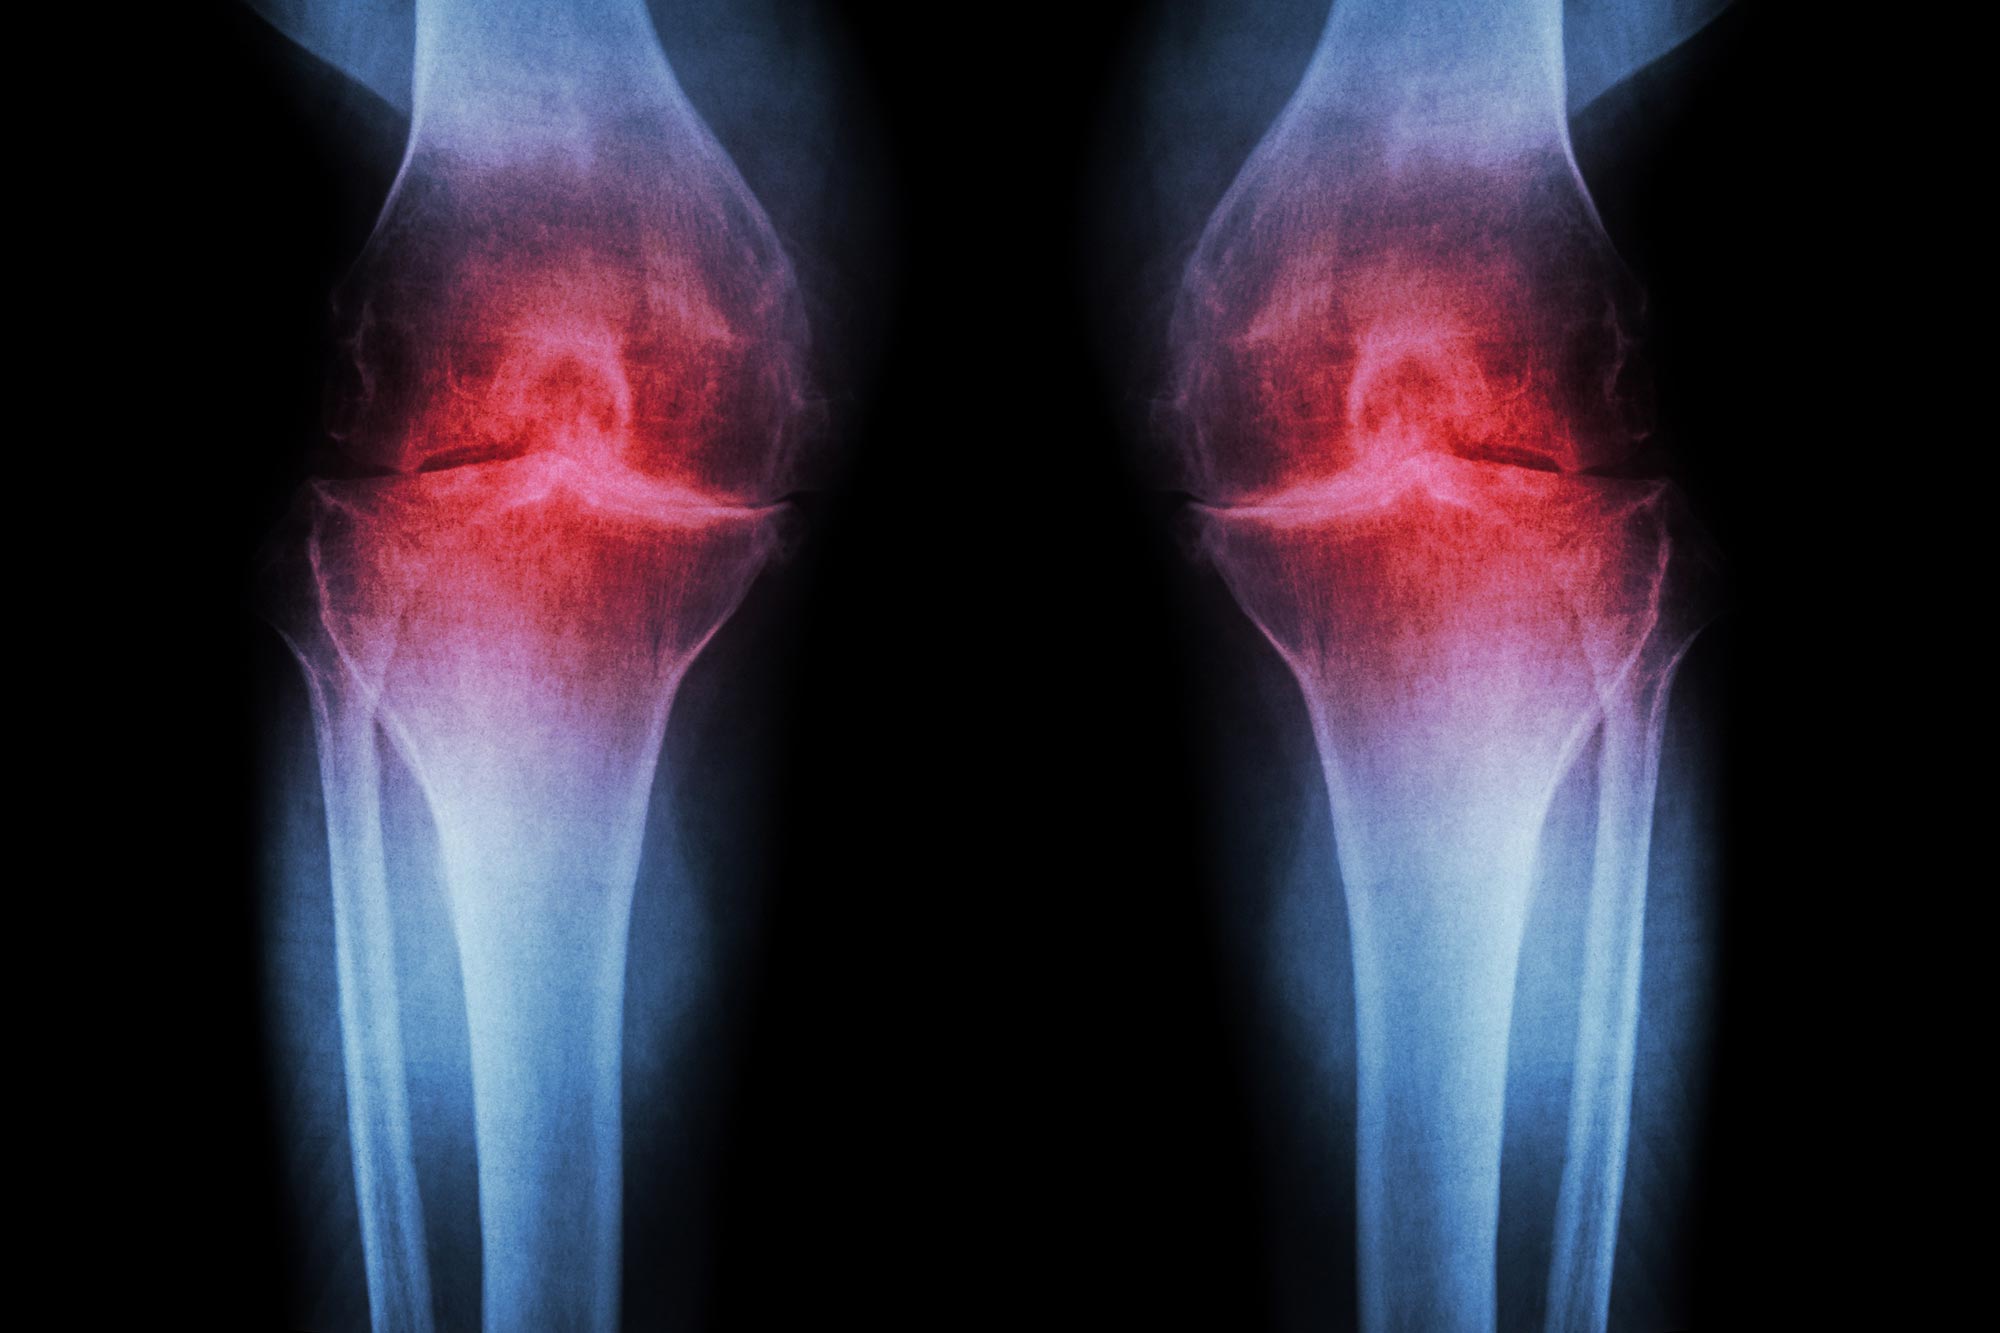

A treatment that blocks an age-related protein restored cartilage in aging and injured joints by reprogramming existing cells rather than using stem cells.